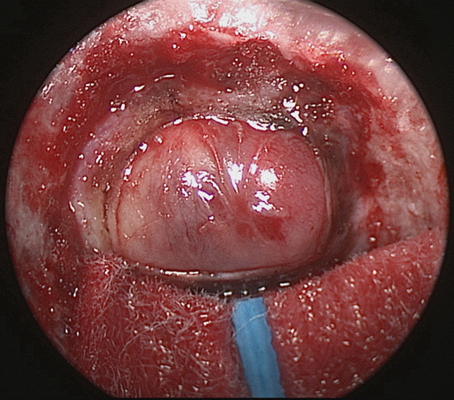

鼻竇炎圖片